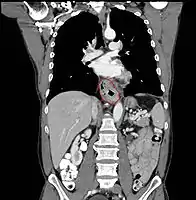

• Lower thoracic esophagus and EG junction:

• Inferior pulmonary veins to the stomach; includes the intraabdominal portion of the esophagus

• By endoscopy, 30 to 40 cm